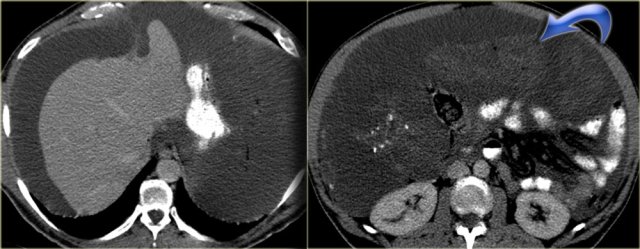

Mesenteric fibromatosis - Desmoid

Mesenteric fibromatosis is also known as intra-abdominal fibromatosis, abdominal desmoid or desmoid tumor.

On the left a 33-year-old man who complains of an increasing abdominal girth, abdominal fullness, and a palpable abdominal mass.

First study the images on the left and continue with the MR.

Look for some imaging features that are helpful in the differential diagnosis.

First of all this is a well circumscribed lesion with a low density on CT.

There is some enhancement around the lesion and there are some small strands of enhancement within the lesion.

On MR there is a low signal on T1 as we would expect.

On T2 there is relatively high signal.

In combination with the low density on CT this tells us that there is mucin within the lesion.

This finding is very suggestive of the diagnosis of mesenteric fibromatosis.

Mesenteric fibromatosis - Desmoid (2)

The enhancement on MR is more intense compared to the enhancement on CT.

On CT the low density of the mucin stands out, but on MR we can appreciate the enhancement better.

It tells us that the lesion is well vascularized.

Mesenteric fibromatosis or desmoid is a benign proliferative process that is locally aggressive and can recur, but it does not metastasize.

The small bowel mesentery is the most common site.

13% of patients have familial adenomatous polyposis (FAP).